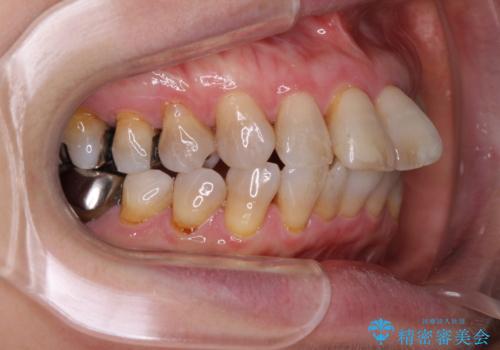

- 口元の突出感と歯の色を気にして来院された患者様です。

口元を引っ込めるために上下左右第一小臼歯4本を抜歯し、ワイヤー矯正を行うこととしました。

歯の色はホワイトニングかセラミッククラウンで対応することとしましたが、ブラックトライアングルが目立つことが予想されたため、目立つ範囲をオールセラミッククラウンで補綴することとしました。